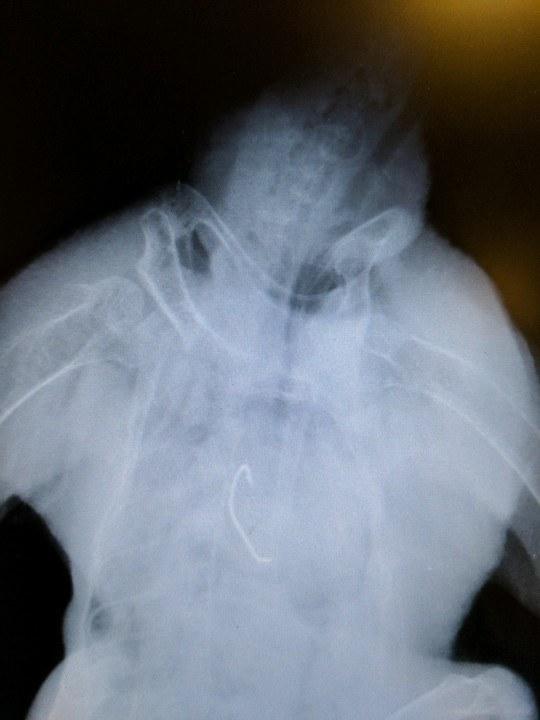

Like we talked about before, there is no way to completely prevent things like this from happening, but just be aware that hooks left in fish can end up in these birds. Photo via Peggy at Umpqua Wildlife Rescue